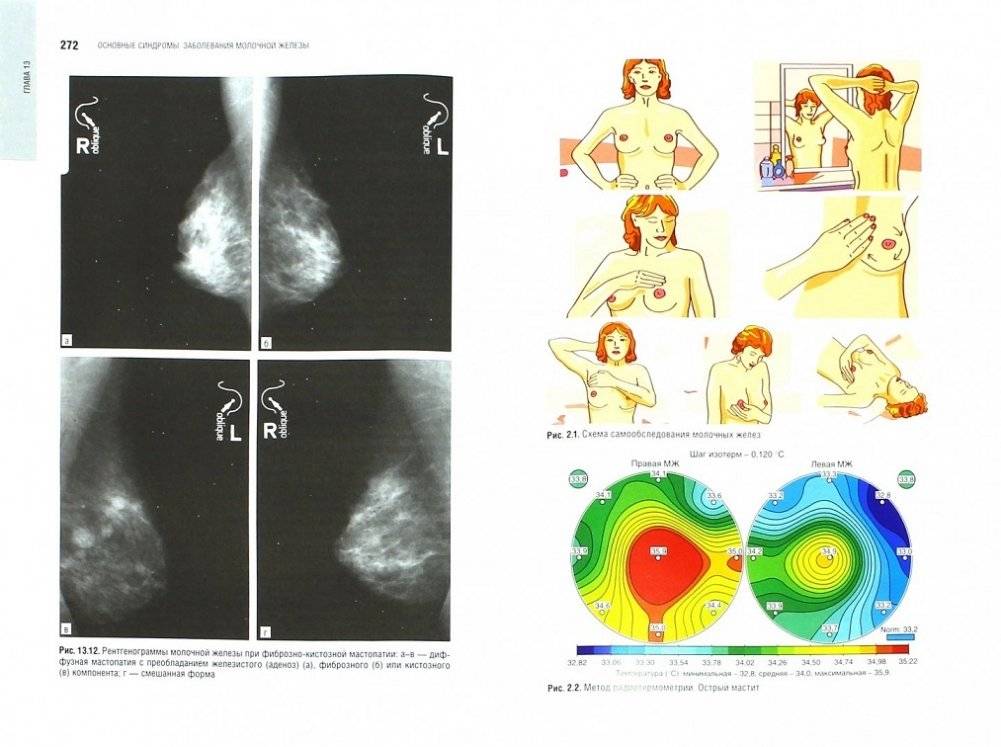

ΠΡΠΎ ΡΡΠΊΠΎΠ²ΠΎΠ΄ΡΡΠ²ΠΎ ΠΏΡΠ΅Π΄ΠΎΡΡΠ°Π²Π»ΡΠ΅Ρ ΡΠΎΠ²ΡΠ΅ΠΌΠ΅Π½Π½ΡΡ ΠΈΠ½ΡΠΎΡΠΌΠ°ΡΠΈΡ ΠΎ Π΄ΠΈΠ°Π³Π½ΠΎΡΡΠΈΠΊΠ΅ ΠΈ Π»Π΅ΡΠ΅Π½ΠΈΠΈ ΠΎΡΠ½ΠΎΠ²Π½ΡΡ Π·Π°Π±ΠΎΠ»Π΅Π²Π°Π½ΠΈΠΉ ΠΌΠΎΠ»ΠΎΡΠ½ΠΎΠΉ ΠΆΠ΅Π»Π΅Π·Ρ, ΠΎΡ Π²Π°ΡΡΠ²Π°Ρ ΠΊΠ»ΡΡΠ΅Π²ΡΠ΅ Π°ΡΠΏΠ΅ΠΊΡΡ ΠΌΠ°ΠΌΠΌΠΎΠ»ΠΎΠ³ΠΈΠΈ. ΠΠ±ΡΠ΅Π΄ΠΈΠ½Π΅Π½ΠΈΠ΅ Π²Π΅Π΄ΡΡΠΈΡ ΡΠΎΡΡΠΈΠΉΡΠΊΠΈΡ ΡΠΏΠ΅ΡΠΈΠ°Π»ΠΈΡΡΠΎΠ² ΠΏΠΎΠ·Π²ΠΎΠ»ΠΈΠ»ΠΎ ΡΠΎΠ·Π΄Π°ΡΡ ΡΡΡΠ΄, ΠΎΡΡΠ°ΠΆΠ°ΡΡΠΈΠΉ ΡΠΎΠ³Π»Π°ΡΠΎΠ²Π°Π½Π½ΡΡ ΠΏΠΎΠ·ΠΈΡΠΈΡ ΠΏΠΎ Π°ΠΊΡΡΠ°Π»ΡΠ½ΡΠΌ Π²ΠΎΠΏΡΠΎΡΠ°ΠΌ ΡΠΎΠ²ΡΠ΅ΠΌΠ΅Π½Π½ΠΎΠΉ Π΄ΠΈΠ°Π³Π½ΠΎΡΡΠΈΠΊΠΈ ΠΈ ΡΠ΅ΡΠ°ΠΏΠΈΠΈ. ΠΠ·Π΄Π°Π½ΠΈΠ΅ ΠΏΠΎΠ΄Π³ΠΎΡΠΎΠ²Π»Π΅Π½ΠΎ ΠΏΠΎΠ΄ ΡΠ³ΠΈΠ΄ΠΎΠΉ Π ΠΎΡΡΠΈΠΉΡΠΊΠΎΠΉ Π°ΡΡΠΎΡΠΈΠ°ΡΠΈΠΈ ΠΌΠ°ΠΌΠΌΠΎΠ»ΠΎΠ³ΠΎΠ² ΠΈ ΠΡΡΠΎΡΠΈΠ°ΡΠΈΠΈ ΠΌΠ΅Π΄ΠΈΡΠΈΠ½ΡΠΊΠΈΡ ΠΎΠ±ΡΠ΅ΡΡΠ² ΠΏΠΎ ΠΊΠ°ΡΠ΅ΡΡΠ²Ρ.